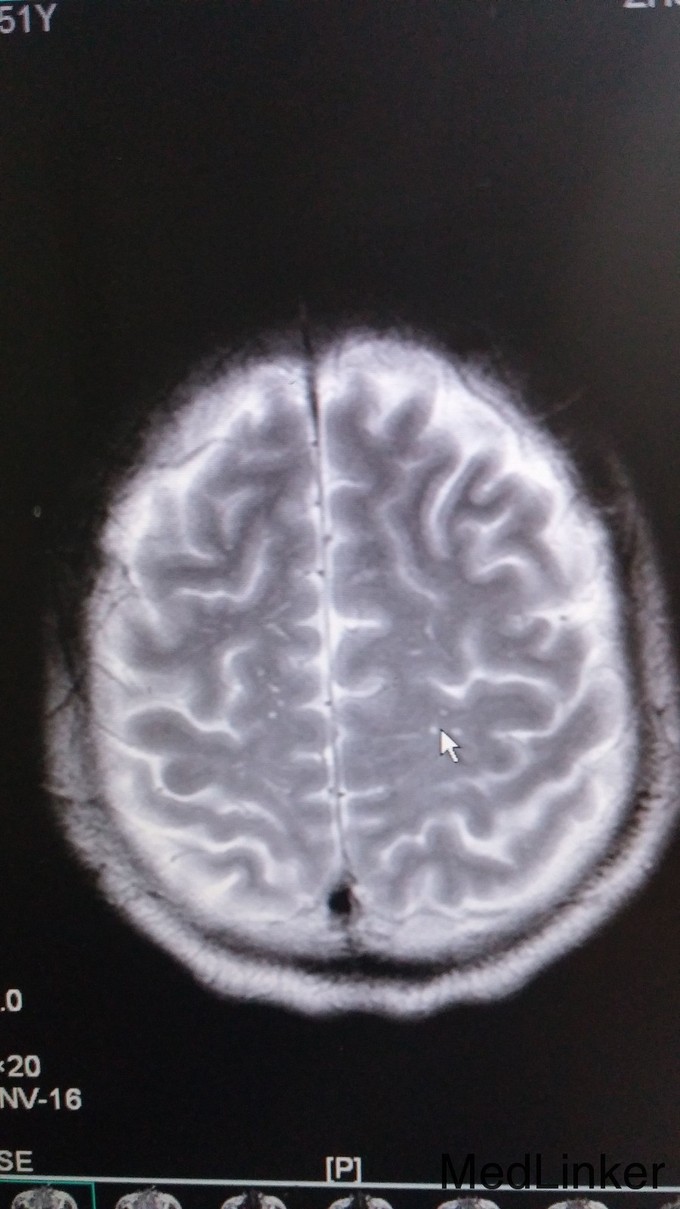

神志昏睡、语无伦次,定向力、判断力正常、计算力、记忆力无法检查。左侧肌张力增高。四肢肌力2级。指鼻、跟膝胫试验检查不配合。双侧腹壁反射存在。双侧肱二头肌、肱三头肌、膝腱、跟腱反射减弱。颈抵抗,颏胸距3横指,Kernig和Brudzinski征阴性。辅查: 1. 血常规:HSCR 3.24mg/L,白细胞计数9.1G/L,中性粒细胞计数8.32G/L,中性粒百分数91.4%;CK 504IU/L, CK-MB 27.9 IU/L, LDH 293 IU/L; 2. 腰穿:脑压225mmH20,氯119.9mmol/L,葡萄糖5.5mmol/L, 乳酸4.7 mmol/L, 蛋白1460 mg/L, 白细胞 60M/L 3. 颅脑MRI:双侧大脑半球(基底节区及放射冠区分布较多)、小脑、桥脑、中脑、延髓多发异常信号灶,增强扫描颅内血管明显增多、迂曲,脑膜增厚强化,可符合播散性脑脊髓炎改变,不排除其内白质疏松及腔隙性脑梗塞因素。肌电图:神经性受损(运动神经为主);脑电图:轻-中度异常脑电图;胸片示:下肺野纹理增粗、模糊,不排除炎症。